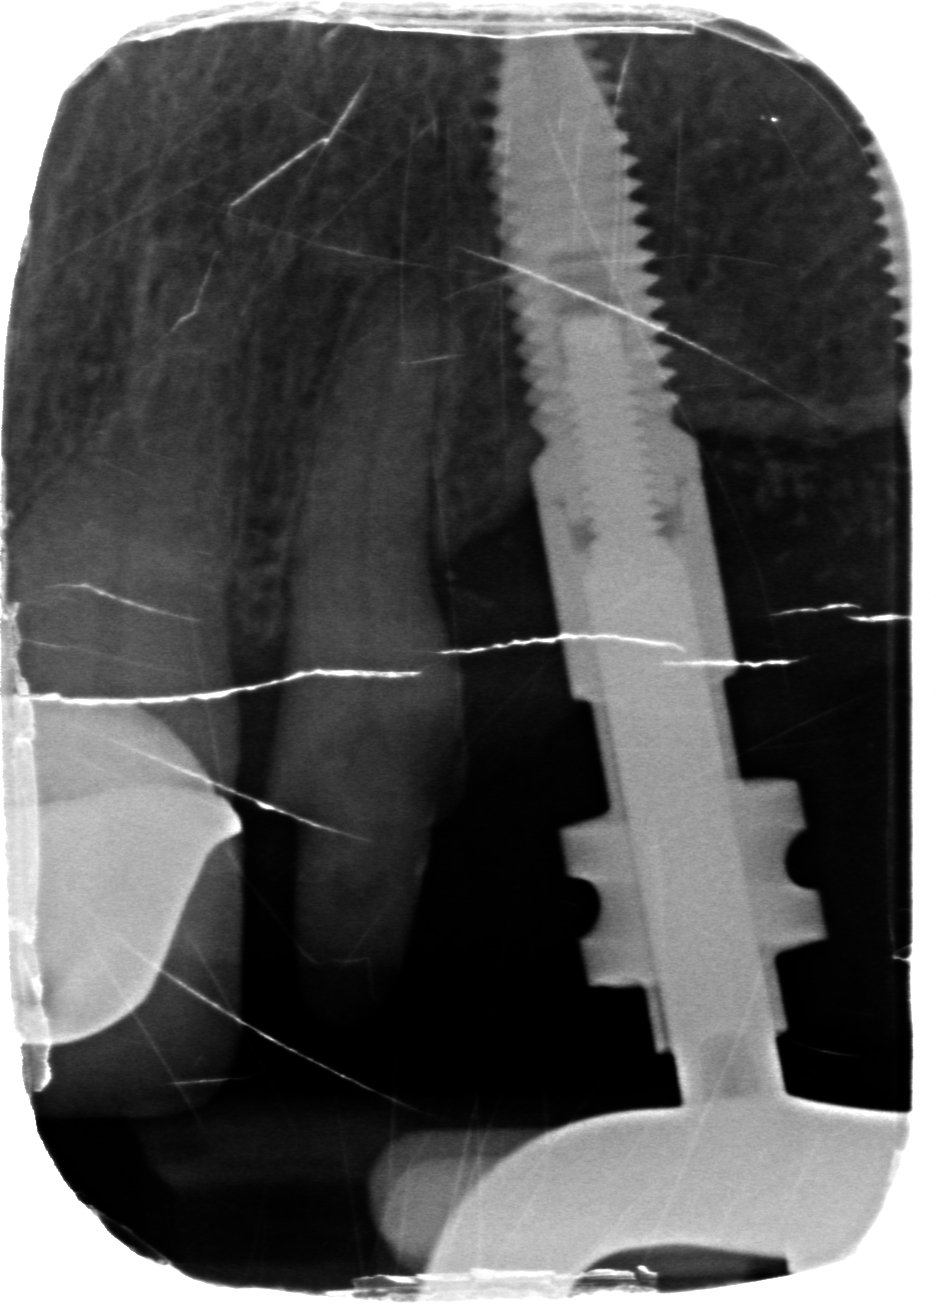

Buenos días, tengo un colega que me preguntó por este caso que le llego a su consulta hace unos días. Le colocaron el implante en España hace mas de 5 [...]